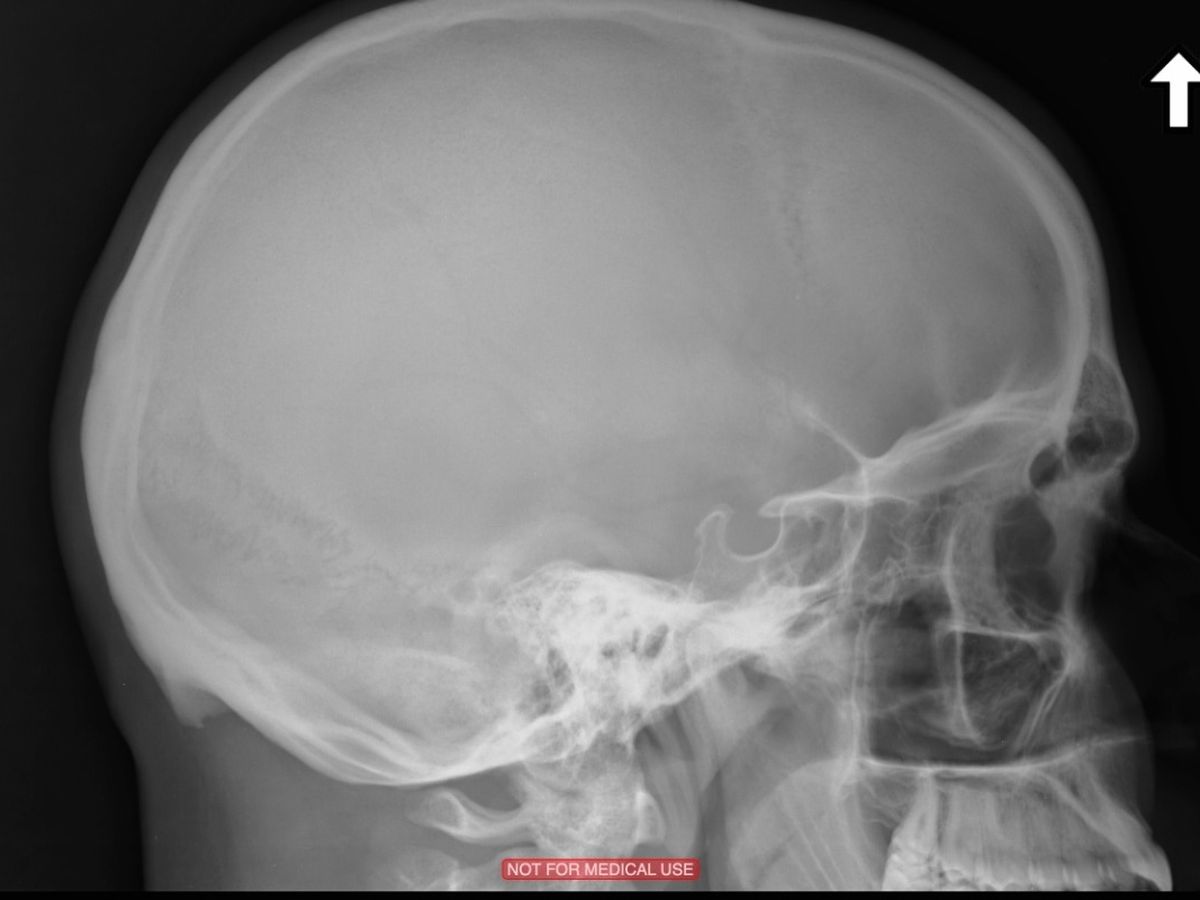

I started transition as soon as I could, back in 2010. Due to endogenous androgens and genetics, I have facial features that are masculinized: my nose, chin, and forehead/supraorbital ridge. Unfortunately, hormonal replacement can only change soft tissue and fat distribution. The bones/cartilage of the face can be surgically reshaped to de-masculinize secondary sexual characteristics in a set of craniofacial/maxillofacial procedures called FFS. FFS is significantly invasive, but almost every clinical study shows a significant increase in patient quality of life after FFS. To clarify, I am not interested in aesthetic/appearance improvements beyond those inherent to de-masculinization. Because of those facial features, I've never taken (nor posted online) any photos of myself. In lieu of a photograph, I've included a sagittal X-ray of my skull which shows most of the structures that will be operated upon (the sensor plate was not big enough to include all of my nose).

I started transition as soon as I could, back in 2010. Due to endogenous androgens and genetics, I have facial features that are masculinized: my nose, chin, and forehead/supraorbital ridge. Unfortunately, hormonal replacement can only change soft tissue and fat distribution. The bones/cartilage of the face can be surgically reshaped to de-masculinize secondary sexual characteristics in a set of craniofacial/maxillofacial procedures called FFS. FFS is significantly invasive, but almost every clinical study shows a significant increase in patient quality of life after FFS. To clarify, I am not interested in aesthetic/appearance improvements beyond those inherent to de-masculinization. Because of those facial features, I've never taken (nor posted online) any photos of myself. In lieu of a photograph, I've included a sagittal X-ray of my skull which shows most of the structures that will be operated upon (the sensor plate was not big enough to include all of my nose).